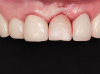

(45.) A patient presented for the replacement of the maxillary left central incisor with a bonded pontic made from the natural tooth, which was removed.

Figure 45